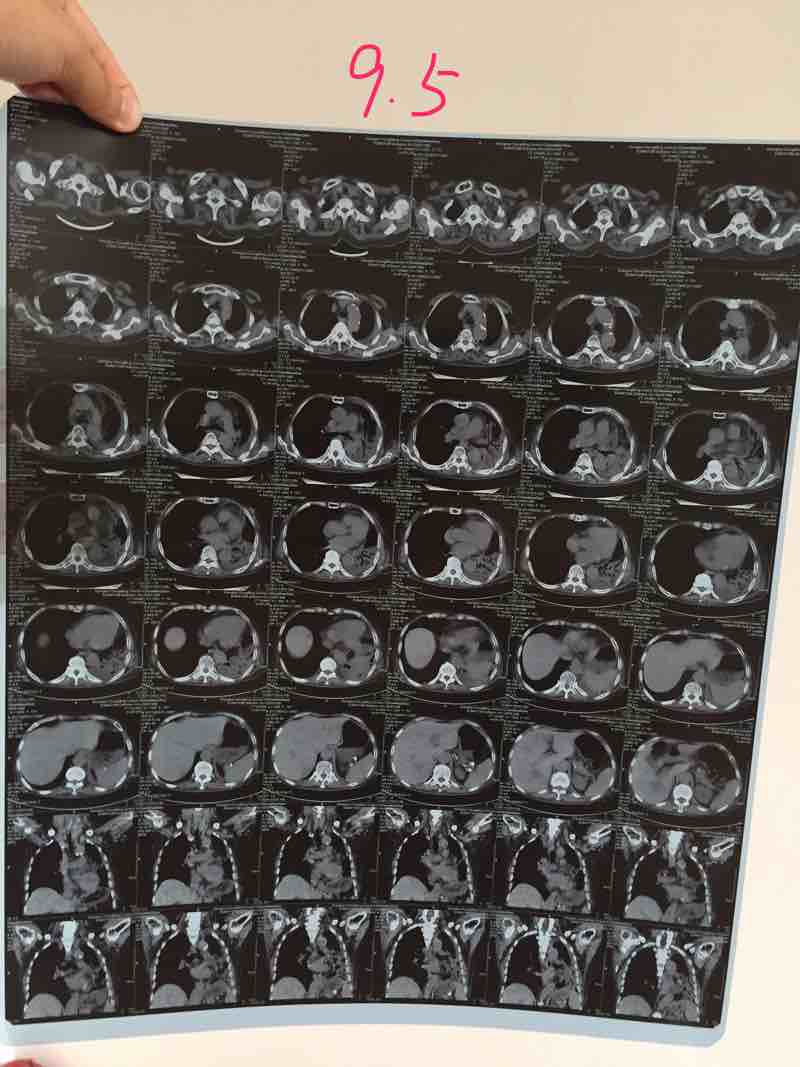

第二点,家属做的资料美观,直观,非常适合医生对比的逻辑判断需要,提出表扬。并允许该患者后续问题在这里额外讨论一周。

资料整得不错,一目了然,值得借鉴。

9月5日

2017-09-11 19:29:56 有用(0)

感觉图片上传之后确实没那么清晰了……